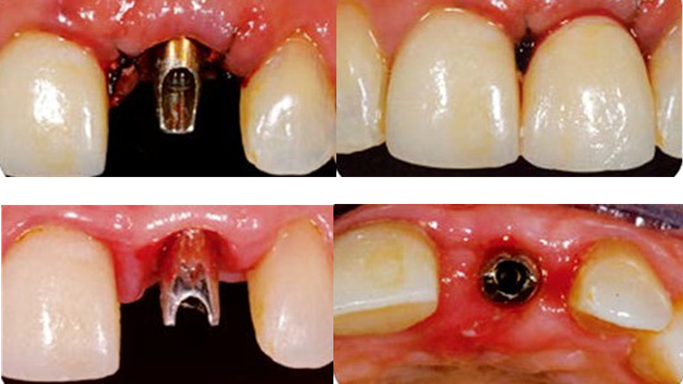

Clinical case: Replacement of fractured central incisor (#11) with immediate implant

& Root Membrane Technique

- Courtesy of Dr. Miltiadis Mitsias, Greece -

AnyRidge, Root Membrane Technique, retrospective study, long-term study, immediate implants, bone resorption, bone preservation, Dr. Miltiadis Mitsias,survival, success, maxillary anterior, single replacement

AnyRidge implant system, Root Membrane kit

The Root Membrane Technique: A retrospective clinical study with up to 10 years of follow-up./Implant Dent. 2018 Oct;27(5):564-574

https://www.ncbi.nlm.nih.gov/pubmed/30161062